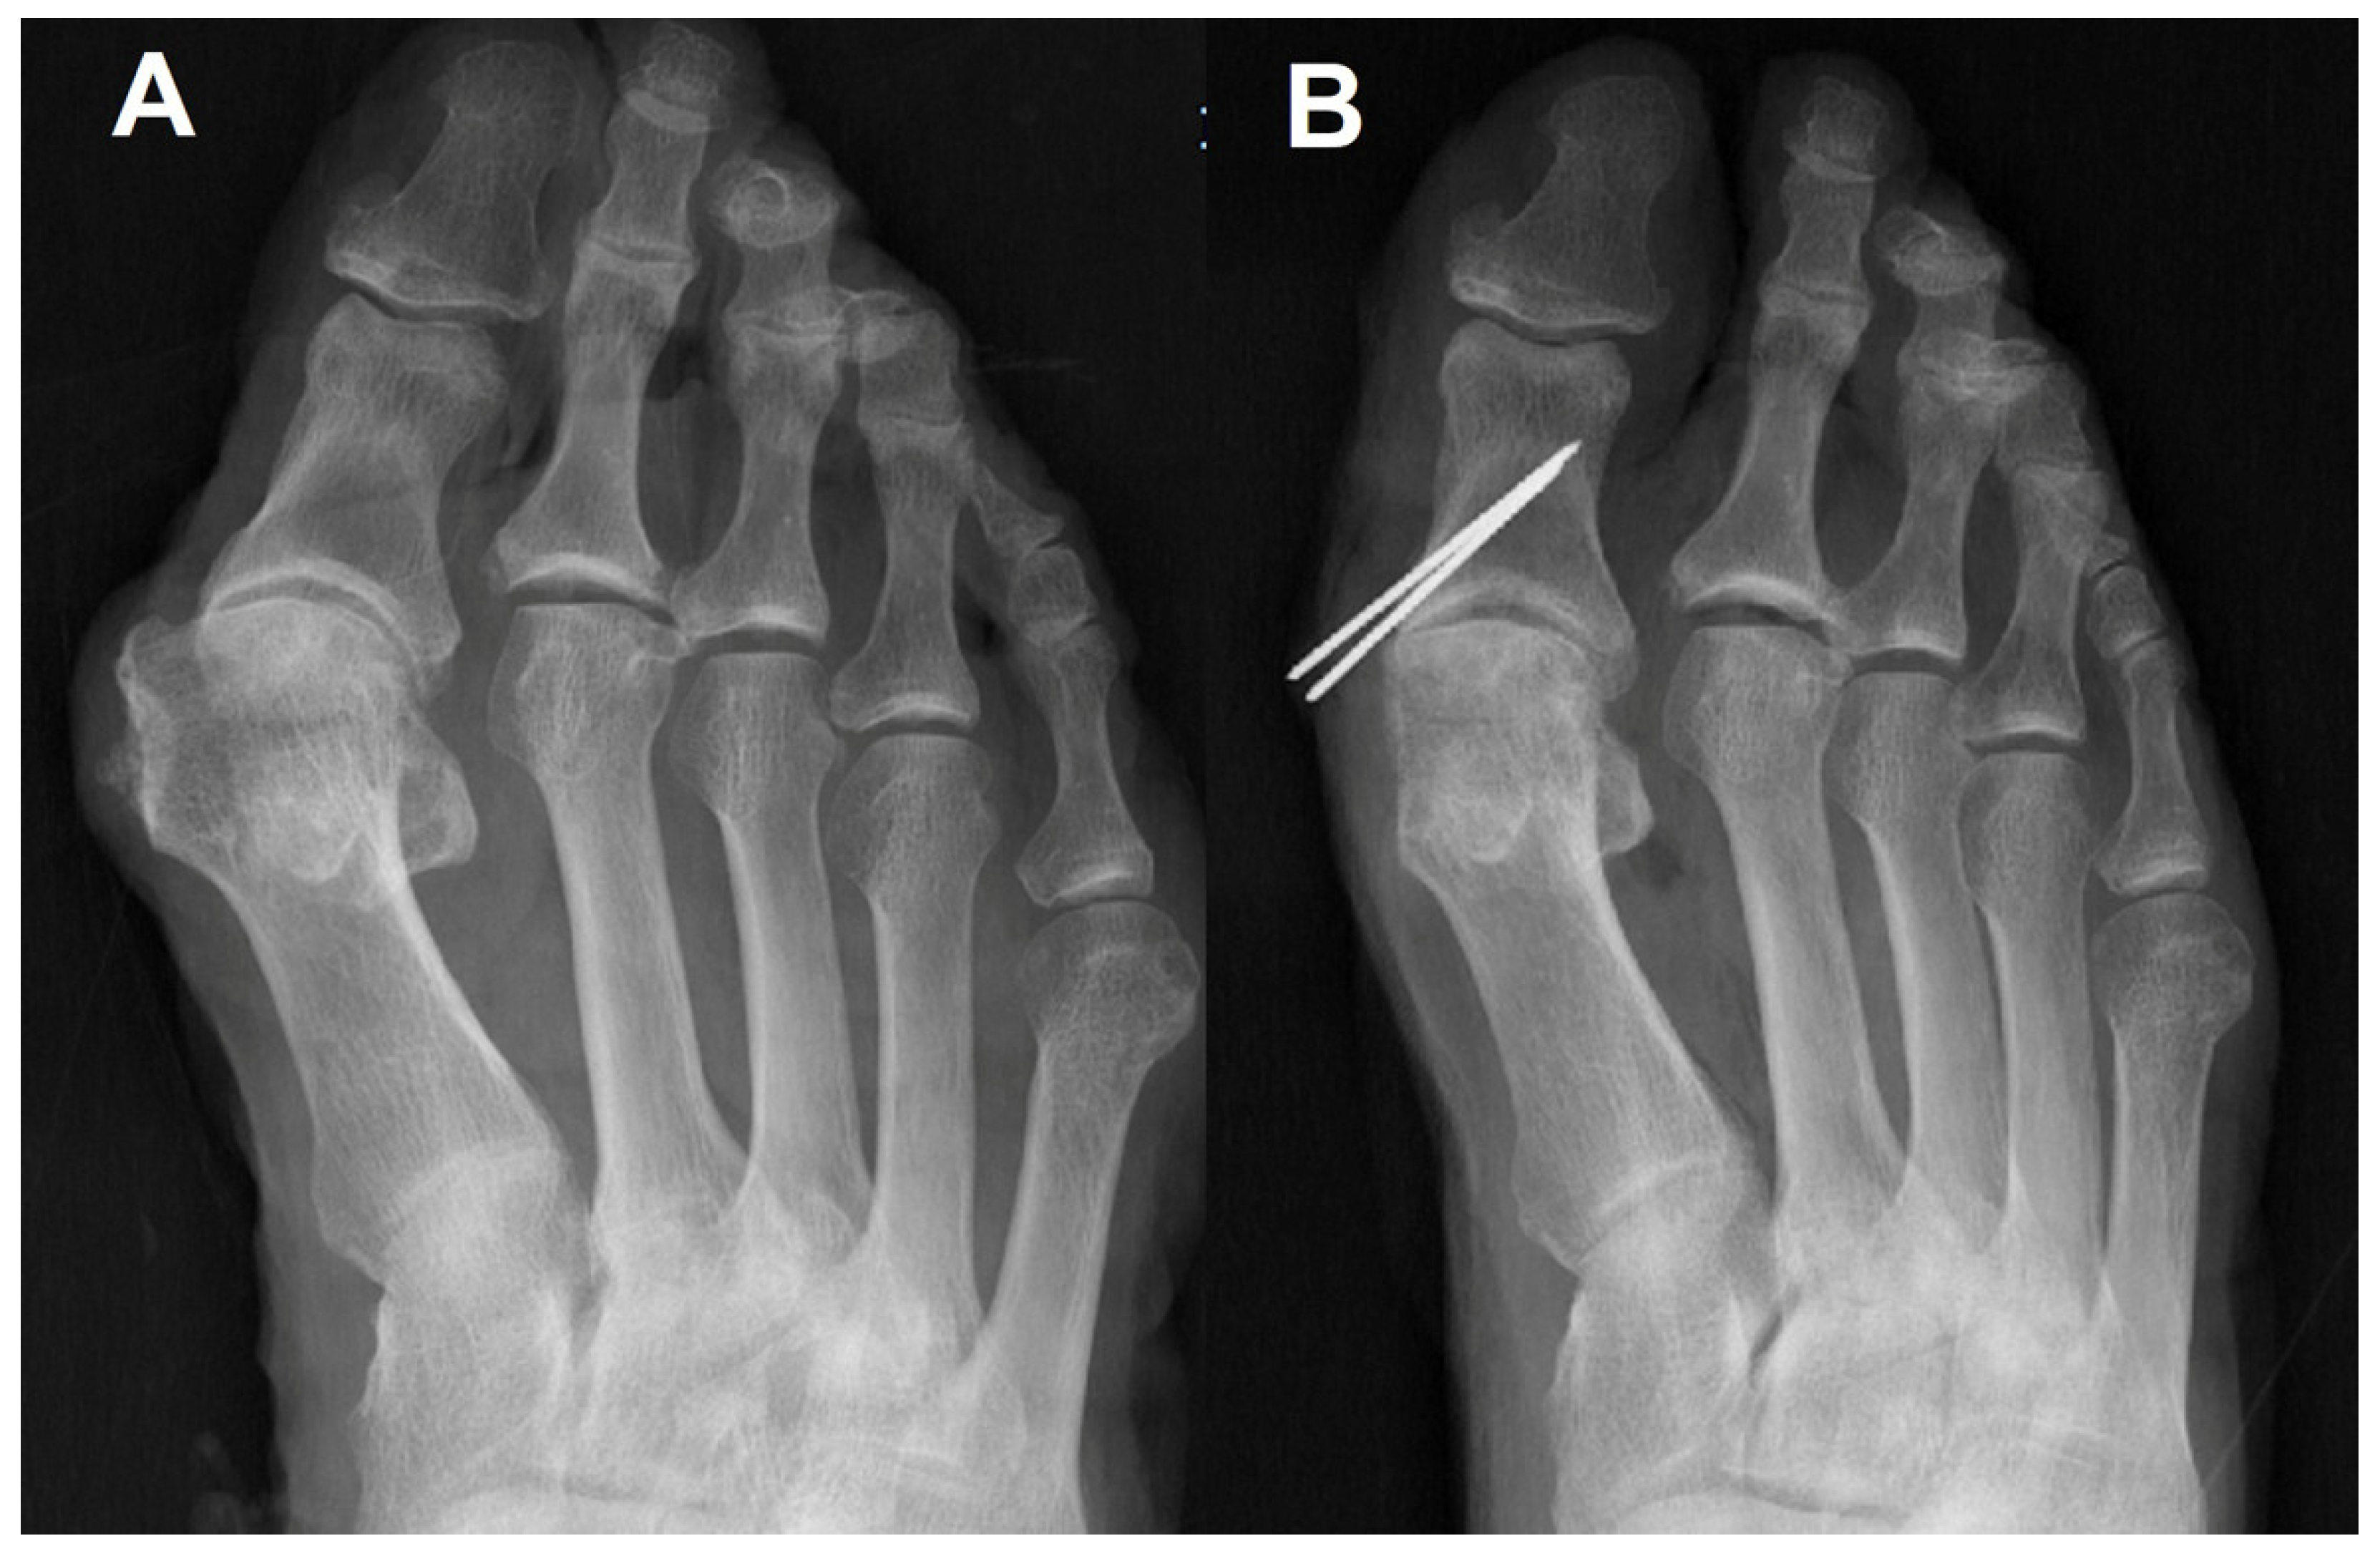

The preoperative/postoperative HVA and IMA are shown in Table 1. Sesamoid positions before/after surgery are demonstrated in Table 2. All radiographic measurements in all the specimens were improved after surgery (Figure 3).

Figure 3. Proximal phalanx osteotomy alone reduces sesamoids to some degree but not perfectly. (A) Preoperative simple radiograph of hallux valgus in cadaver; (B) Modified proximal phalanx osteotomy was performed. Bunionectomy was done for making K-wire entry point.